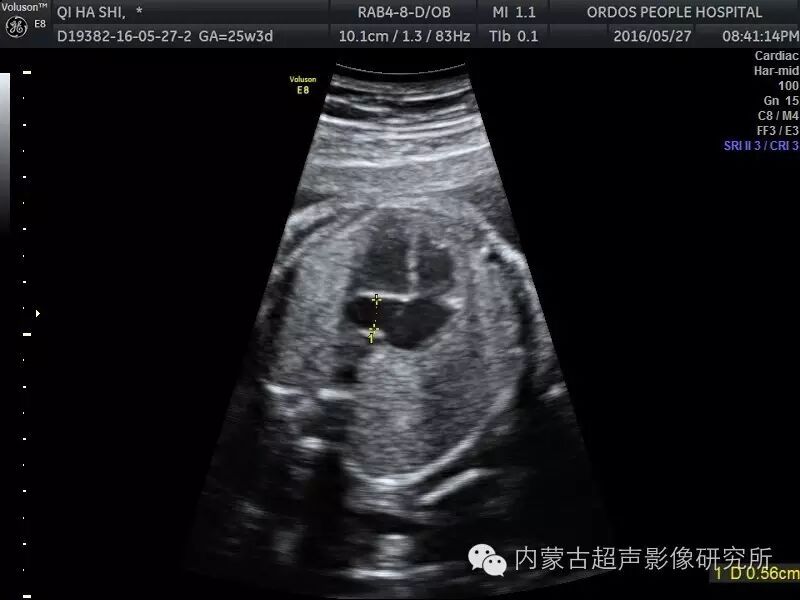

胎儿永存左上腔静脉

胎儿永存左上腔静脉,

一,永存左位上腔静脉

再谈永存左上腔静脉plsvc

病例报告:超声诊断胎儿永存左上腔静脉一例